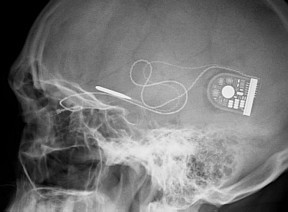

Microchip capaz de transformar a luz em impulsos elétricos que o cérebro consegue reconhecer foi implantado detrás da retina de pacientes que sofriam de doença degenerativa

Um microchip de três milímetros, capaz de transformar a luz que penetra no globo ocular em impulsos elétricos que o cérebro consegue reconhecer, foi implantado detrás da retina dos pacientes, que ficaram cegos devido a uma doença degenerativa.